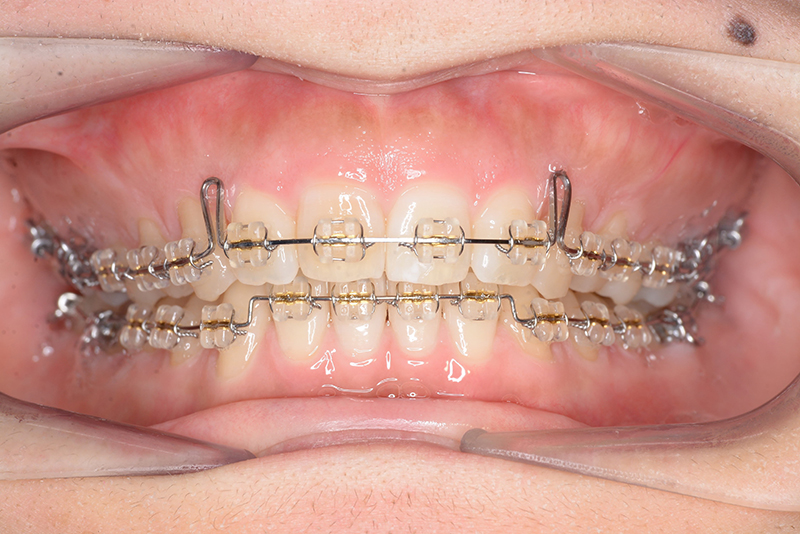

動的治療時(PLASによる上顎歯列遠心移動)

動的治療時

(PLASによる上顎歯列遠心移動)

IOP